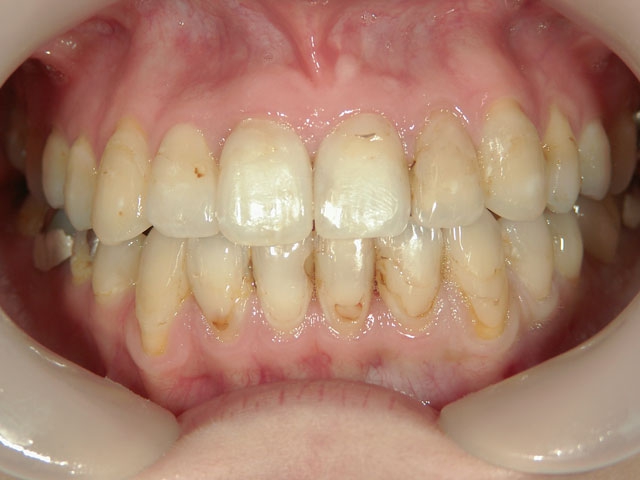

no.7_6967_治療前_右_01.jpgno.7_6967_治療後_正面_01.jpgno.7_6967_治療前_左_01.jpg

no.7_6967_治療後_右_01_640_480_やや高画質.jpgno.7_6967_治療後_正面_01.jpgno.7_6967_治療後_左_01.jpg